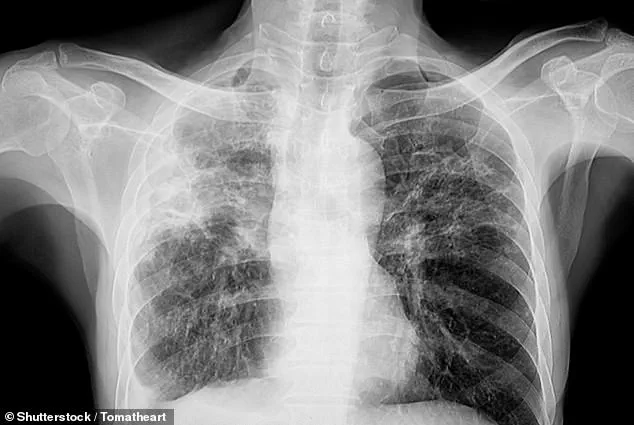

The disease, which causes irreversible scarring of lung tissue, is often associated with symptoms like shortness of breath and chronic coughing.

Pulmonary fibrosis, a progressive and often fatal condition, is typically linked to exposure to asbestos, dust, or mold, as well as autoimmune diseases and certain medications.